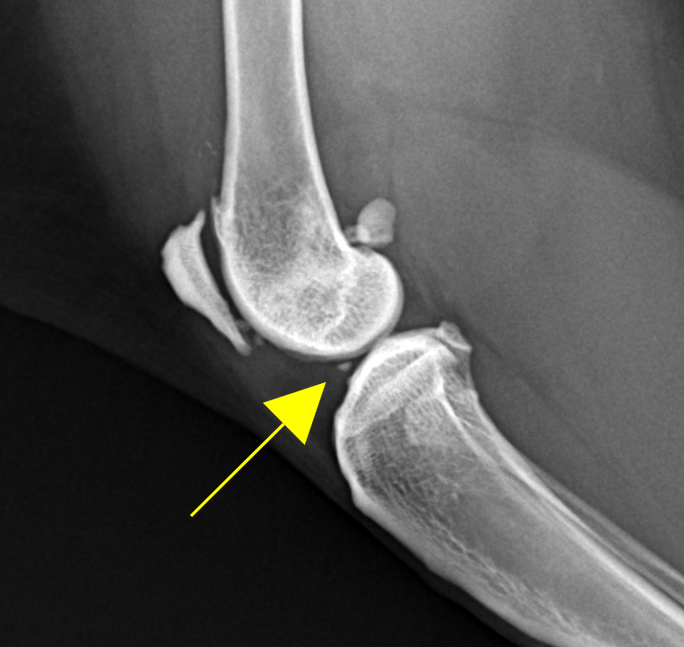

feline joint mice radiography sample